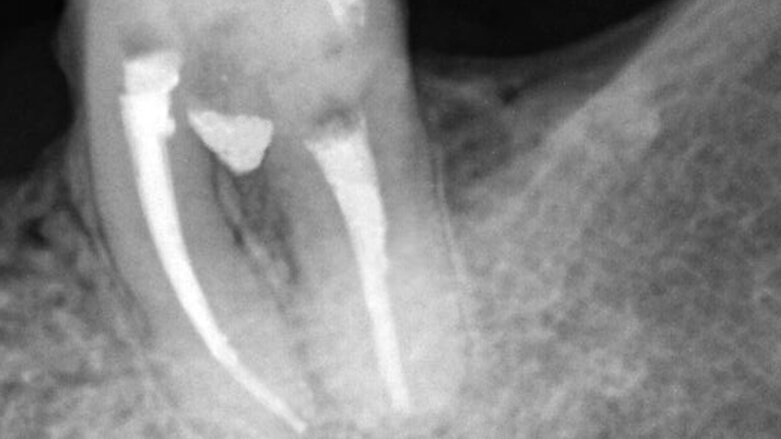

Figs. 4: Clinical and radiographic appearance of drilling filling with MTA Repair HP.

Figs. 5: Clinical and radiographic appearance of drilling filling with MTA Repair HP.

After 15 days, again, we proceeded to seal the drilled region, and initially verified the proper possibility of drying the area. The filling of the drilled region was carried out with the use of MTA Repair HP (Angelus/Brazil), previously prepared as recommended by the manufacturer, and it was inserted using an MTA Applicator (Angelus/Brazil). Clinical and radiographic criteria were used to determine the correct filling using the material (Figs. 4 and 5); and the glass ionomer cement (Vitremer/3M/USA) used for the protection of the sealed region (Fig. 6). After the temporary restoration, radiographically it was observed proper sealing of furcation region by MTA Repair HP, as well as no postoperative complications.